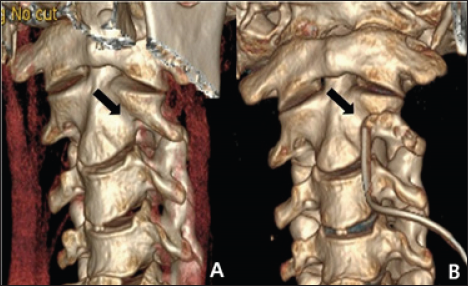

Figure 3: A. Preoperative CT 3D-reconstruction image. B. The postoperative CT 3D-reconstruction image showed that the anterior portion of the transverse foramen had been removed; the foramen was thus widened while preserving the articular facet (black arrow).

The patient was placed in the supine position with his head slightly extended via Holter traction. A transverse skin incision was created on the medial border of the sternocleidomastoid muscle at the C2-3 level. After dissecting the prevertebral muscles, the C2 vertebral body, left transverse process, and left VA were exposed. The anterolateral portion of the left transverse foramen that covered the VA was carefully drilled. The bony spicule at the lateral curvature of the VA just below the C2 transverse process was also removed. The anterior half of the bony structure surrounding the VA was fully decompressed, and VA pulsation immediately became more active. Postoperative CTA showed a wider transverse foramen than preoperatively (Figure 3). The symptoms improved dramatically after surgery. Neck movement was not limited, and no cervical spine instability was evident on a dynamic X-ray.